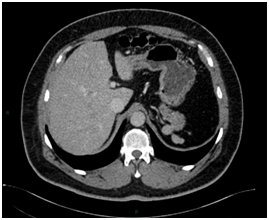

Intrahepatic splenosis shows increased enhancement on CT or MR images during the arterial phase. Performing gadoxetic acid–enhanced hepatocyte-phase MR imaging does not help because intrahepatic splenosis is hypointense during the hepatospecific phase. The MR technique involving administration of small iron oxide particles (SPIO-Endorem), which is taken up by liver and spleen reticuloendothelial cells, has proven to be effective in differentiating intra-hepatic splenosis from other lesions.14,15,18 With SPIO (superparamagnetic iron oxide) intrahepatic splenic nodes remain hyperintense.19 Noncontrast CT reveals a well circumscribed iso- or hypodense mass in the liver, while noncontrast MRI demonstrates mild-to-moderate hyperintensity on T2-weighted image and hypointensity on the T1-weighted image. A dynamic study on CT and MRI shows a slight to intense enhancement, which may be homogeneous or heterogeneous during the arterial phase but enhancement is diversely during the portal venous and equilibrium phases in different cases. Compared with the surrounding hepatic parenchyma, the lesion could reveal hypodensity and hypointensity, or hyperdensity in the arterial phase. Or it can demonstrate diminished enhancement, slight enhancement, or increased enhancement during the following phases (Figure 2 & 3).19,20

Figure 3Postoperative figures A, B, C, D and E. Computed Tomography (CT). Postoperative CT in the axial plane in the post-contrast venous phase show signs of partial resection of the liver segment II (A,B, C and D), as well as splenectomy with small implants of splenic tissue in the left subphrenic region (E).